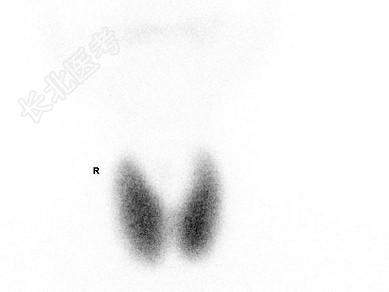

- 单项选择题99TcmO4-甲状腺静态显像如图,最可能诊断为 ( )

A、甲状腺功能亢进

B、甲状腺瘤

C、桥本氏病

D、甲状腺功能亢进或者甲状腺功能低下

E、亚急性甲状腺炎